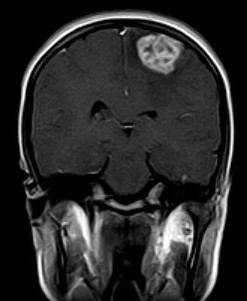

September 2005 - Intracerebral Tuberculomas

There is a conglomeration of lesions in the right temporo-parieto-occipital and left frontal lobes. These are hypointense on the T2W images and reveal a whorl or bunch of grapes type of enhancement. Note is made of perilesional edema.

On MRI

On plain MRI, granulomas usually appear isointense to gray matter on the T1W images and may have a slightly hyperintense rim (probably due to the presence of paramagnetic substances). On T2W images, the tuberculomas exhibit variable signal. They are often isointense or hypointense to brain parenchyma and it is postulated that this relative hypointensity is related to T2 shortening by paramagnetic free radicals produced by macrophages, which are heterogeneously distributed throughout the caseous granuloma. The diminished signal on T2W images may also be due to the mature tuberculoma being of greater cellular density than brain. Granulomas may also be hyperintense to brain on T2-weighted images; this is likely due to a greater degree of central liquefactive necrosis in these lesions. Edema surrounding tuberculomata is relatively more prominent in the early stages of granuloma formation.

Post contrast (gadolinium) images of TB granulomas demonstrate intense nodular and ring-like enhancement. Healed tuberculomas may calcify in up to 20% of cases and these are usually more evident on CT than MRI. On MRI, the calcifications are more evident on gradient-echo than on spin-echo imaging. Atrophy is frequently a long-term sequelae of tuberculous CNS infection. Full resolution of cerebral tuberculomas requires months to years of medical therapy. The length of time required is related more to the size of the original lesion than to any other single factor.